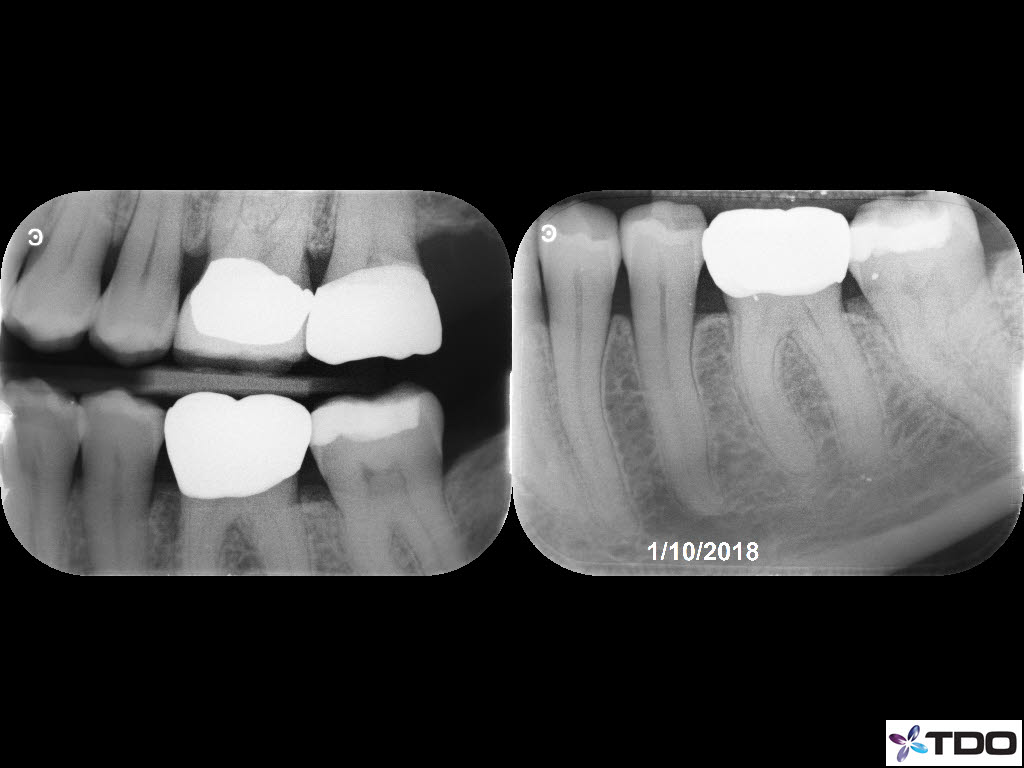

From last week. 59yof. SIP. Hyperemic. 6 canals. 2 visits. Asymptomatic at the second visit. Asymptomatic and functional at the follow-up appointment.